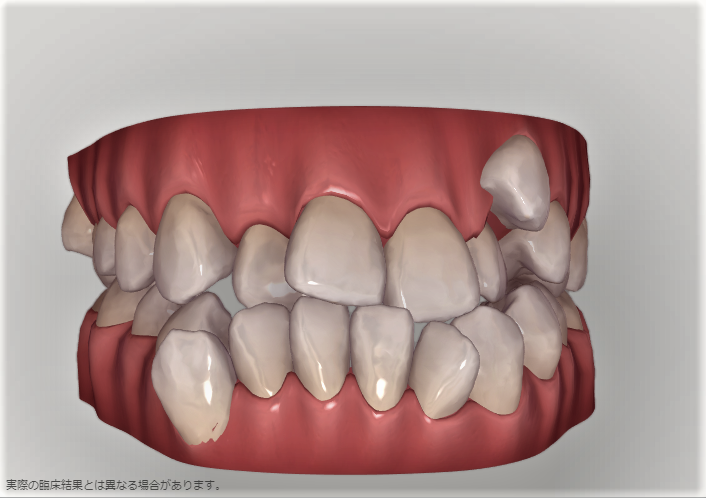

下の歯にも同様に引っ込んだ歯がある。

下の歯。こちらも歯並びの中に納まっている。

下の歯の比較